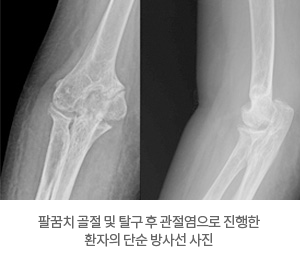

- └ 팔꿈치 관절염

- └ 팔꿈치 강직

팔꿈치 강직

팔꿈치 관절 불안정증